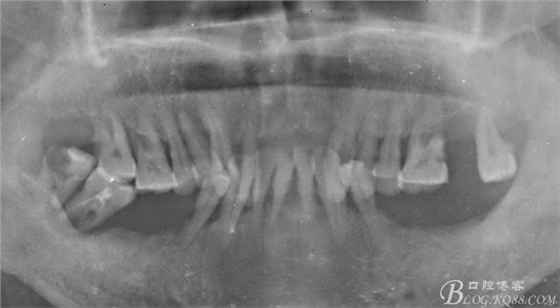

病人上前牙缺失,下頜前牙伸長(zhǎng)已經(jīng)咬到上頜牙槽脊,看x線片

牙槽骨嚴(yán)重吸收,全口牙還剩下21顆牙,但是 在1度松動(dòng)的牙齒只有12顆牙,其它牙都在2度到3度松動(dòng)之間

上頜--15、13、23、24、25

下頜--44、43、42、41、32、33、34